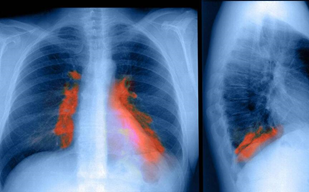

1、第一大并发症-肺部感染

股骨颈骨折后卧床至少6周到3个月,而且骨折之后疼痛,没法翻身。人一不动,肺里的痰就出不来,时间一长,肺就感染。